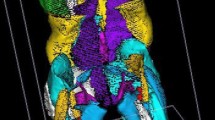

3D Muscle Reconstruction

The 3D reconstruction of individual muscles, listed in Table 1, was performed using Muscl’X software (ENSAM, Laboratory of Biomechanics, Paris, France), a validated software [9] already employed in previous literature [10]. Some muscles were combined, since the low contrast made an accurate separation of the individual muscles difficult. The lumbar part of the psoas was reconstructed separately, but at a point where the distinction with the iliacus was not possible, it was then integrated into the iliacus. The external obturator, adductor longus, brevis and magnus and pectineus were reconstructed into a single group named “Adductor.” The vastus lateralis and intermedius were reconstructed together. The muscle reconstructions were done on the fat images. Figure 1 (reprinted with permission from the authors of previous literature [10]) presents the 3D reconstruction of the left muscles for one patient. The femurs were also reconstructed on the water images; the contrast between the cortical and cancellous bones was greater on water images.

Medial and frontal view of all the left muscles reconstructed for one patient. (Reprint with permission from [10])

Right and left muscles were grouped according to the joint (spine, hip and knee) and by mechanical action \(\left( {\frac{{{\text{Flexor}}}}{{{\text{Extensor}}}}{\text{of spine}},{\text{ hip and knee}}} \right)\) (Table 1). The function of muscles is summarized in Table 1, while the function of gluteus medius and minimus was left empty due to their complexity.